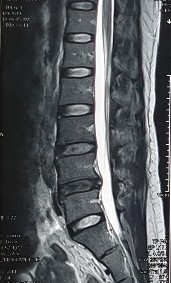

1. Hình ảnh khảo sát dẫn truyền thần kinh, điện cơ đồ và MRI (thực hiện trên mẫu nghiên cứu: bệnh nhân Nguyễn Văn H., mã số bệnh nhân 731711).

Bệnh nhân H., khi khám lâm sàng có biểu hiện tổn thương rễ thần kinh L3, L4, L5. Kết quả xét nghiệm điện cơ thấy: dẫn truyền thần kinh bình thường, nhưng kết quả khi điện cơ kim có biểu hiện tổn thương rễ thần kinh L4 . Kết quả chụp cộng hưởng từ là tổn thương thoát vị L4 – L5 . Như vậy, trên bệnh nhân này vị trí tổn thương thực tế khi kết hợp phối hợp giữa khám lâm sàng, chẩn đoán hình ảnh và chẩn đoán chức năng là vị trí rễ thần kinh L4.

Hình ảnh thoát vị đĩa đệm trên phim chụp MRI.